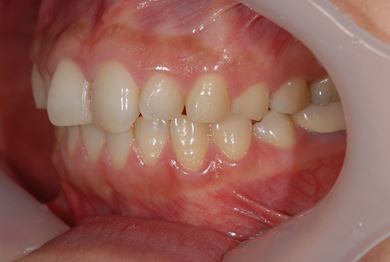

インプラント治療+セラミック治療+歯肉歯槽骨整形

| 性別/年齢 | 女性 / 38歳 | ||||||||||||||||||||||||||||||||

| 主訴 | 右下奥の欠損のため、インプラントを希望。また、左に物が挟まりやすいための治療も希望。 | ||||||||||||||||||||||||||||||||

| 治療方針 | 欠損部分を、インプラント治療にて、機能的・審美的回復を行う。 | ||||||||||||||||||||||||||||||||

| 治療内容 | インプラント1本、ジルコニアフレームオールセラミッククラウン2本(ジルコニアセラミック用土台1本)、歯肉歯槽骨整形 | ||||||||||||||||||||||||||||||||

| 総治療費 | 713,580円 | ||||||||||||||||||||||||||||||||

| 治療期間 | 10ヶ月 |